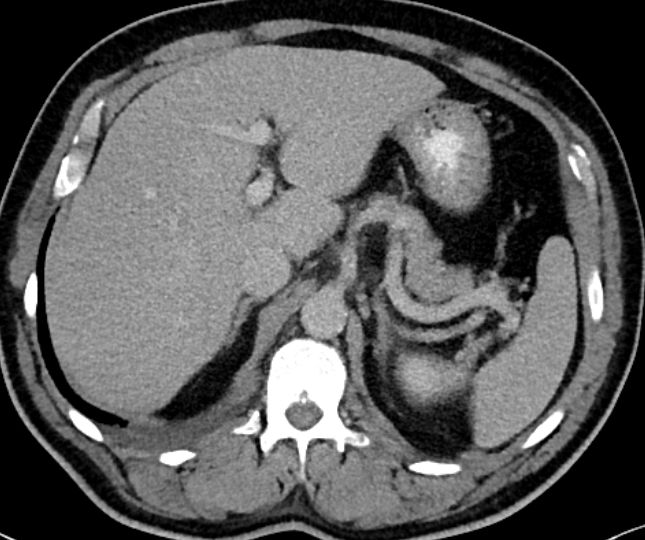

Arteria mesenterica superior und Vena portae